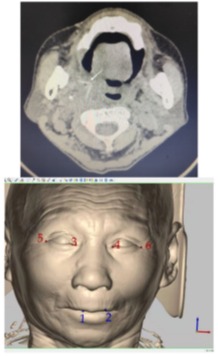

图1术前颌面部CT影像及导航规划图,上图剪头所指为异物

患者程某某,安徽岳西人,8个月前因务农时不慎摔倒致毛竹插入口腔,先后求治于当地县、市两级医院,分别行保守、手术治疗后,患者仍觉口内疼痛不适,影响张口,辗转多地后于来到我院口腔颌面外科求治。患者入院后积极完善相关检验检查,颌面部CT示:右侧口咽旁软组织明显增厚,伴线样异物影。经治疗组孙明副主任医师评估后发现,异物滞留时间长且位于腭咽部软组织内,毗邻众多重要解剖结构且术野受限,异物能否找到、找到后能否完整取出、如何把损伤降到最低均是对外科医生的挑战。

经过科室讨论,在科主任后军及薛浩伟主任医师的积极指导下,决定在计算机辅助导航系统引导下对该患者行腭咽部异物取出术。经过术前精准设计、术中适时定位,在孙明副主任医师、赵丽主治医师等口腔颌面外科医护人员的共同努力下,将患者滞留体内8月余、长约5cm的直角形毛竹完整取出。手术仅历时64分钟,腭咽部术区切口仅长约1 cm,术后3天就已康复出院。孙明副主任说到,以往的口内取异物手术仿佛“大海捞针”,而现在有了计算机辅助导航系统,仿佛多了一双“天眼”,可以精确制导,大大减小了手术创伤,缩短了手术时间,达到了微创治疗的目的。